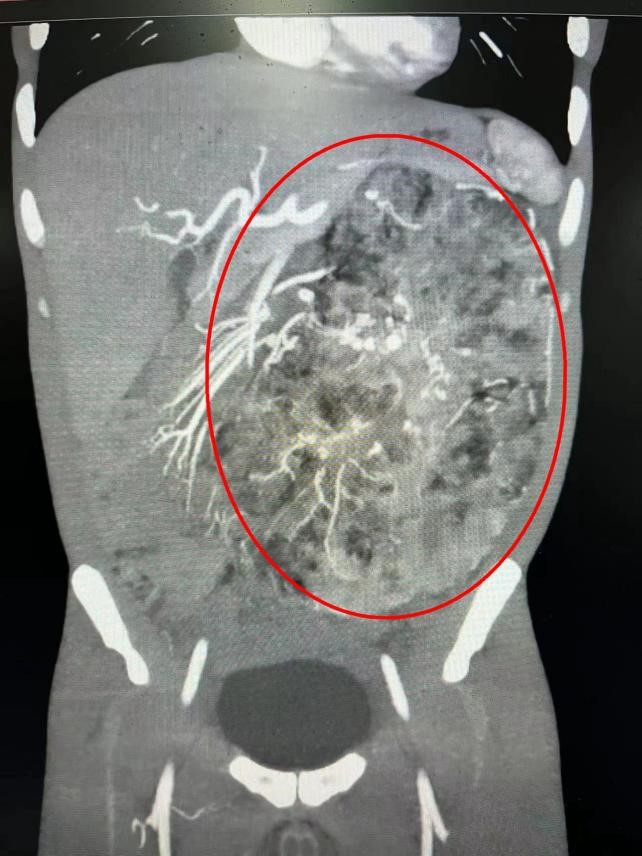

经进一步的CT检查,肿瘤起源于左侧肾脏中下部,考虑为左肾血管平滑肌脂肪瘤。肿瘤体积巨大,上顶肝面,下达盆腔,横跨中线,把腹腔内的肠道都推挤到一隅。当地医生建议罗先生手术治疗,术中可能需要切掉左肾。

为实现患者心愿,陈玢屾教授想尽办法,为患者安排了详细的检查,利用3D重建影像技术,清晰地显示出肿瘤的立体轮廓、血管分布以及肿瘤和肾脏的相对关系,并联合泌尿外科学术带头人刘春晓教授共同完成这一复杂的“拆弹”手术。